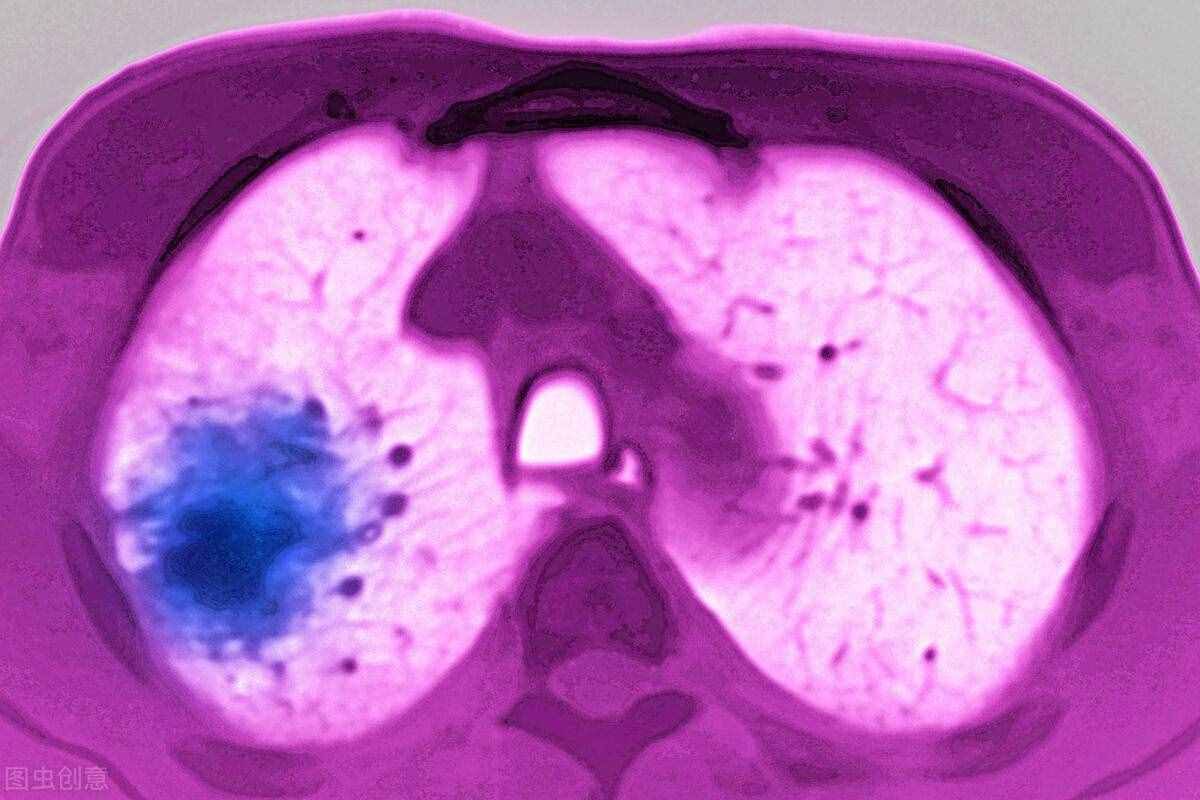

肺癌饮食(肺癌患者饮食怎么吃)